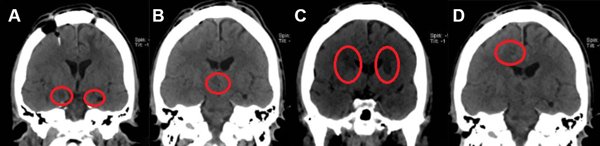

A finales de 2021 acuden nuevamente al Hospital General de México por un TNA refractario y tricofagia, la calificación OAS fue de 16 puntos. Dada la gravedad del cuadro requirió sujeción mecánica en domicilio por lo que se planteó la 3° cirugía límbica. En mayo de 2022 se realizó la tercera neurocirugía psiquiátrica y se efectuaron una hipotalamotomía posteromedial derecha, una amigdalotomía bilateral (2 lesiones de cada lado), una capsulotomía bilateral (3 lesiones de cada lado) y una cingulotomía anterior derecha (2 lesiones). No se efectuó una cingulotomía izquierda porque se presentó una resistencia cerebral al paso del electrodo en este último blanco quirúrgico, probablemente debido a una variación debida a “brain-shift”. En total se realizaron 13 lesiones ablativas por radiofrecuencia. (Figura 2) Las primeras horas de postoperatorio las cursó con buena evolución postoperatoria, presentó somnolencia de 4 horas aproximadamente. Se mantuvo afebril y sin déficit neurológico, los exámenes de laboratorio tuvieron parámetros normales y se registró un poliuria transitoria sin necesidad de tratamiento por lo que se egresó del hospital a las 24 horas. Al mes de la intervención, en junio de 2022, el paciente presenta puntaje en OAS de 0-2, sin tricofagia, con menor ingesta de alimentos por inapetencia. Se presentan datos demográficos en la Tabla 1.

Figura 2. TC de Cerebro postoperatorio en cortes coronales correspondiente al caso 2. Neurocirugía ablativa multitarget. A. Amigdalotomías bilaterales. B. Hipotalamotomía posteromedial derecha. C. Capsulotomías anteriores bilaterales. D. Cingulotomía anterior derecha.9